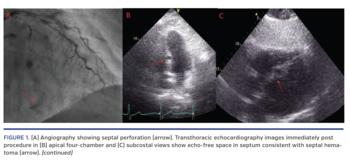

Transthoracic echocardiography immediately post procedure demonstrated an echo-free space in the septum with no evidence of intracardiac shunting consistent with a septal hematoma (Figures 1B and 1C). This was confirmed on gated computed tomography scanning (Figure 1D). Electrocardiogram showed no evidence of cardiac conduction delay and the patient remained stable and was discharged the following day. Repeat echocardiography and cardiac computed tomography performed 6 weeks later showed complete resolution of the hematoma (Figures 1E and 1F).